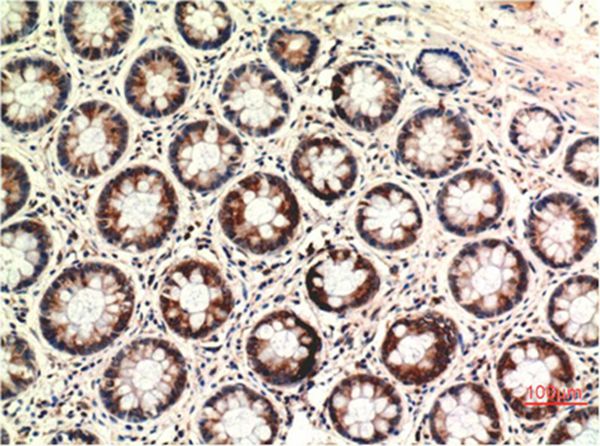

Immunohistochemical analysis of paraffin-embedded Human Colon Carcinoma Tissue using PTEN Mouse mAb diluted at 1:200.

Immunohistochemistry: 1:100-1:200